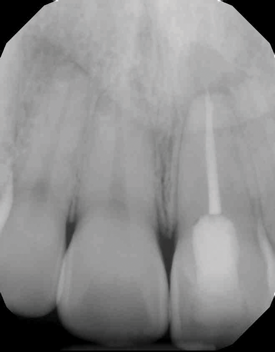

(9.) Preoperative radiograph of previously treated tooth No. 9, which received a diagnosis of acute apical abscess secondary to childhood trauma and recurrent endodontic pathology.

Figure 9

(10.) Posttreatment radiograph and cone-beam computed tomography (CBCT) scan following nonsurgical root canal re-treatment that resulted in incomplete resolution of symptoms in response to percussion and palpation.

Figure 10

(11.) Posttreatment radiograph and cone-beam computed tomography (CBCT) scan following nonsurgical root canal re-treatment that resulted in incomplete resolution of symptoms in response to percussion and palpation.

Figure 11

(12.) Postoperative radiograph after apical surgery was performed using MTA as an apical retrofilling material.

Figure 12

(13.) Normal healing was noted clinically and radiographically at the 6-month follow-up appointment.

Figure 13

Apical Surgery

Apical surgery, which is used to address recurrent or persistent endodontic pathoses, involves root-end resection followed by the placement of a root-end or retrograde filling material (Figure 9 through Figure 13).18,19 Clinical comparative studies have clearly established the greater predictability of surgical procedures that utilize bioceramics when compared with those that utilize alternative materials, such as amalgam or zinc oxide eugenol cements.18,19 As a result, bioceramics are considered the gold standard root-end filling materials.